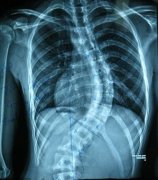

强直性脊柱炎是风湿免疫科常见病,给很多患者造成巨大困扰。医生 ...

日常生活中,骨科疾病实在是太过于常见了,而其中,强直性脊柱炎 ...

强直性脊椎炎的发生会产生很多的症状,可是很多人不知道自己是怎 ...